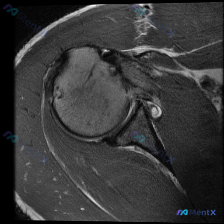

这个肩关节MRI T1序列,首先要先排除什么问题?

看到一份肩关节MRI的病例材料,是T1加权序列的冠状位图像。用户想了解盂唇病变的可能性,先整理一下目前能看到的信息:

- 解剖结构清晰,肱骨头、关节盂、肩胛骨、肩峰都显示良好

- 冈上肌肌腱从肌腹到肱骨大结节止点连续

- 关节盂唇形态尚可,但T1序列对细微病变的敏感度有限

- 肱骨头后上方靠近大结节处,有小斑片状高信号

- 肩峰下间隙无明显狭窄,肩峰形态正常